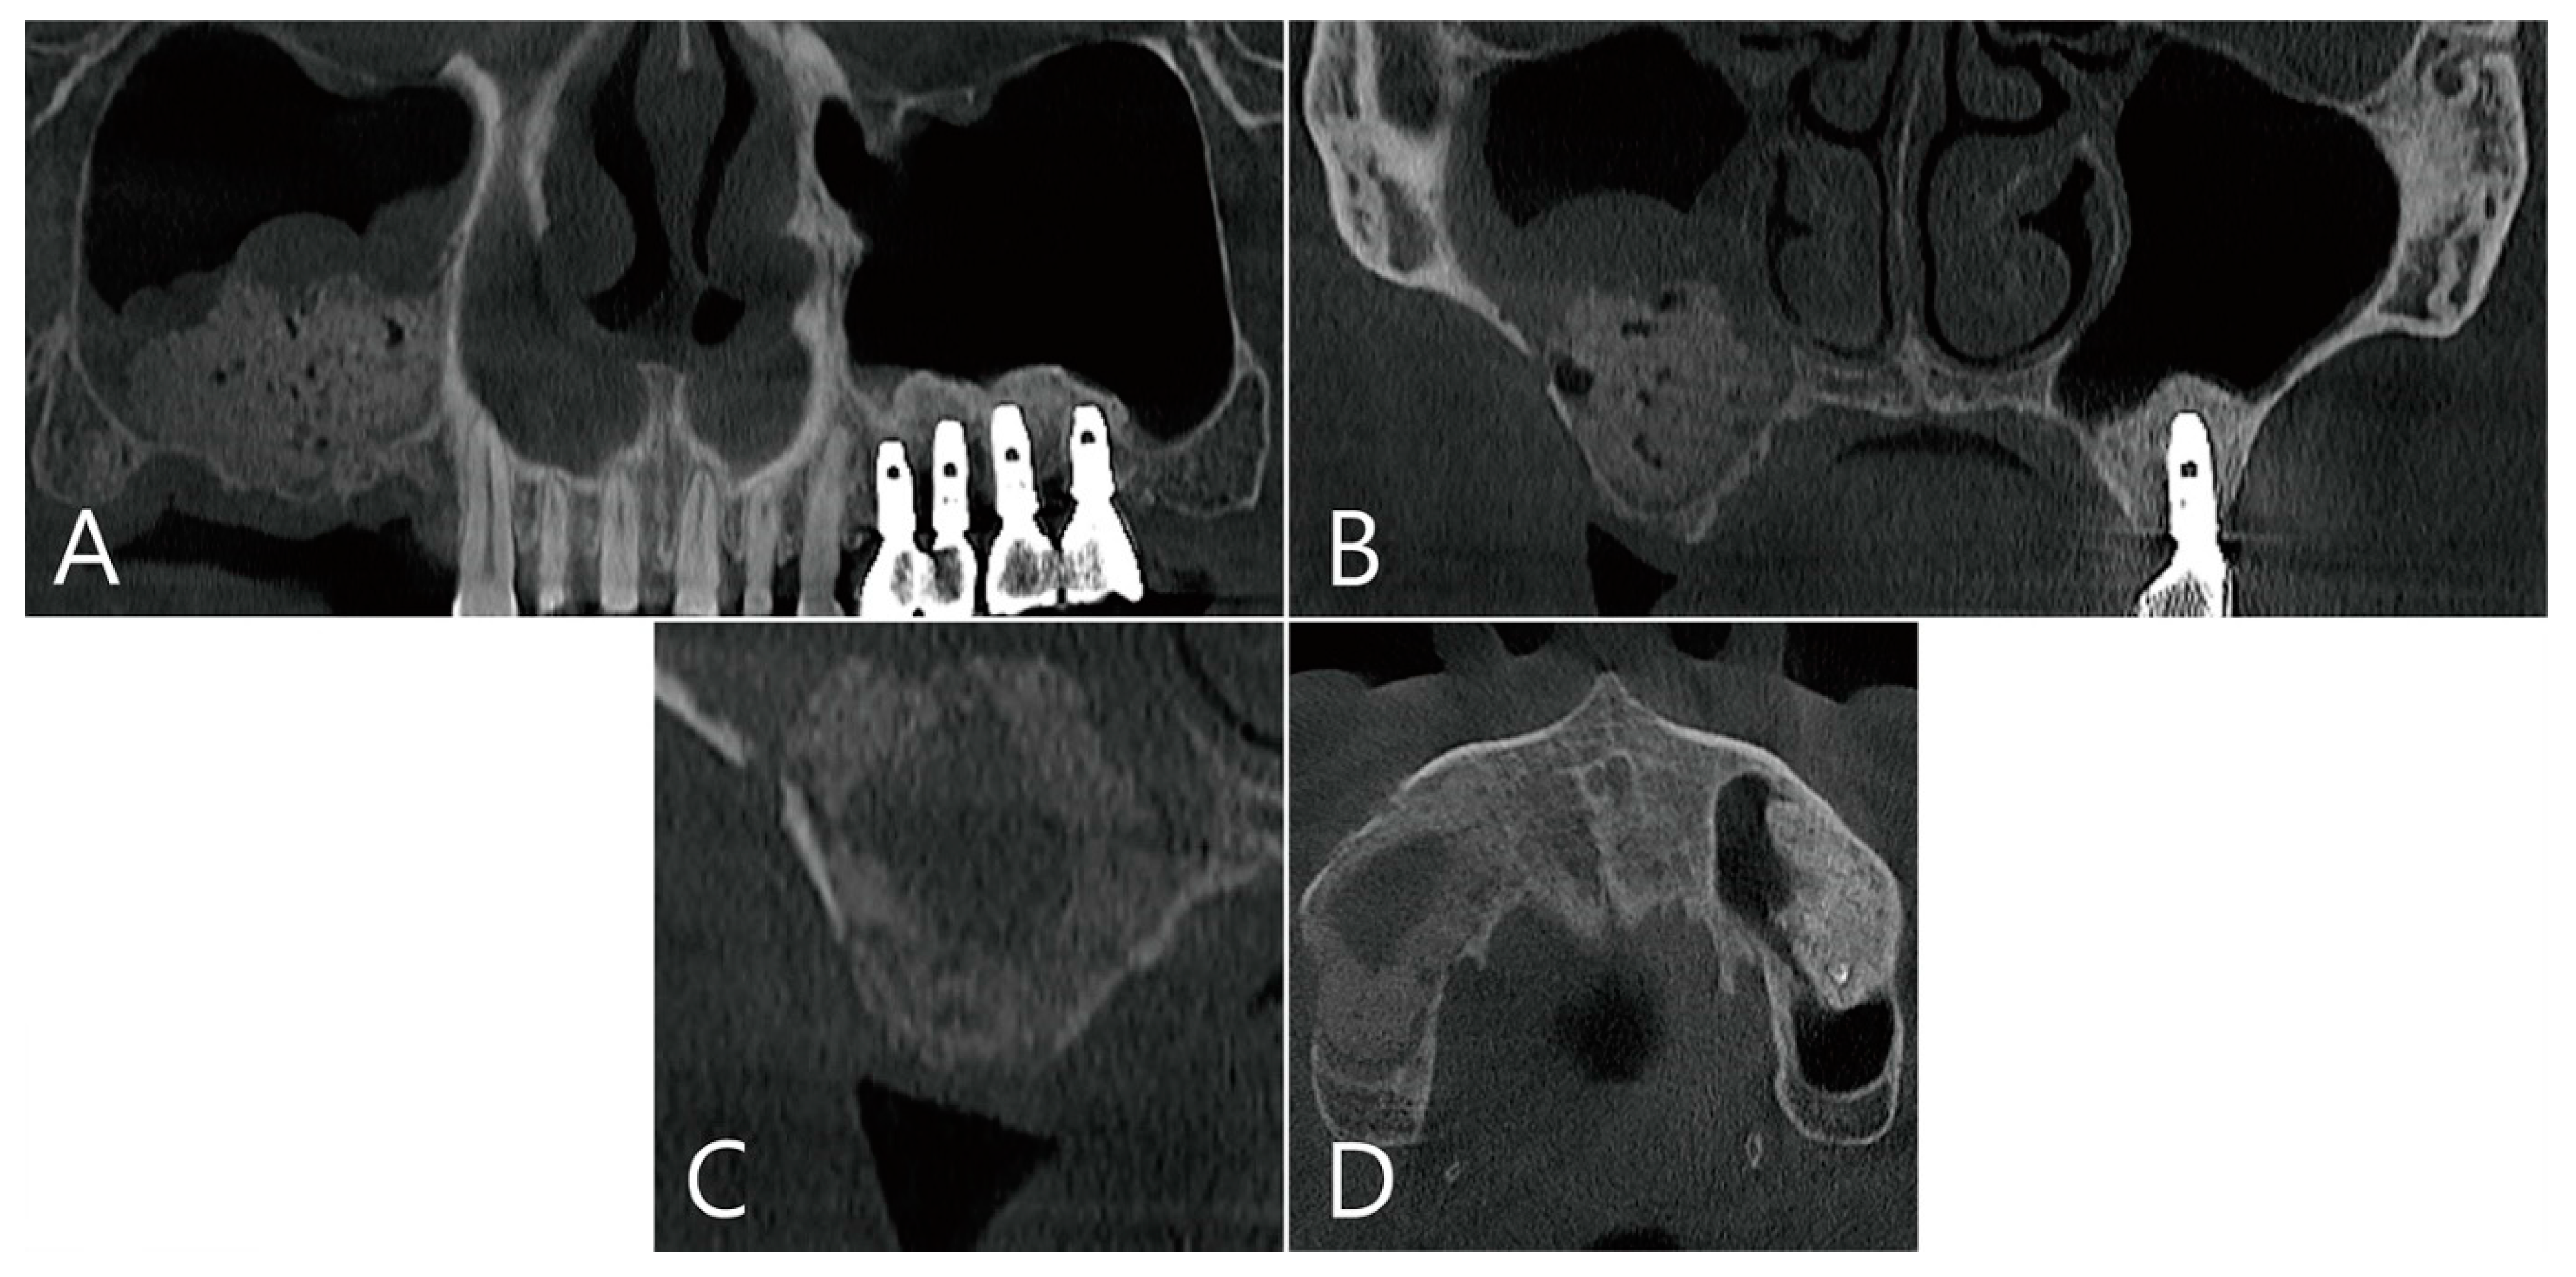

2.5. Case 4

A 75-year-old female who was a non-smoker visited a private clinic to have the implant placed in the edentulous ridge of the maxillary left posterior region (Table 1). This patient was taking antihypertensive and antihyperlipidemic drugs. Preoperative panoramic radiography and CBCT scan were performed. The left maxillary sinus was severely pneumatized and had a minimal residual bone height of 2–4 mm, rendering normal implantation impossible (Figure 10A,B). In the maxillary sinus, membrane thickening was confined to the sinus floor and no sinus pathology was observed in the remaining areas (Figure 10B). Lateral MSA and simultaneous implant placement were planned on the left maxillary sinus.

The coronal image of the CBCT scanned at the #27 implant site was examined. In the image taken immediately after surgery there was no leakage of bone graft particles (Figure 13A), however, a very large grafting void appeared in the image taken one week after surgery (Figure 13B). This grafting void showed a cystic appearance at the implant apex, although its size was reduced on CBCT taken after six months (Figure 13C). On the CBCT taken two years after the grafting void was removed, the grafting void was replaced with new bone (Figure 13D).

Figure 13. The coronal image of the CBCT scanned at the #27 implant site was examined: (A) in the image taken immediately after surgery, there was no leakage of bone graft particles; (B) however, a very large grafting void appeared in the image taken one week after surgery; (C) this grafting void showed a cystic appearance in the implant apex, although its size was reduced on CBCT taken after 6 months; (D) in CBCT taken 2 years after the grafting void was removed, the grafting void was replaced with new bone.